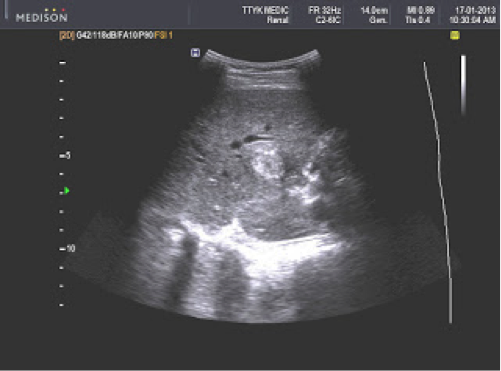

Bệnh nhân nữ 24 tuổi, chậm kinh 2 tuần, nghi có thai nhưng siêu âm tử cung không thấy túi thai trong tử cung hoặc khối cạnh tử cung.

Siêu âm phát hiện ở gan có ổ tròn đậm âm, kích thước 1,86cm, ở giữa có dịch.

Xét nghiệm β-hCG: 34.000 IU/L.

CT: có một ổ trong gan gần túi mật kích thước 2cm, ở giữa khối có dịch (giảm âm), được cung cấp máu từ động mạch gan.

Chẩn đoán thai dưới gan. Điều trị tiêm MTX, sau 2 tuần, xét nghiệm β-hCG trở về bình thường, không cần can thiệp ngoại khoa. Kết quả tốt do phát hiện sớm (Phan Thanh Hải và cs., 2007).